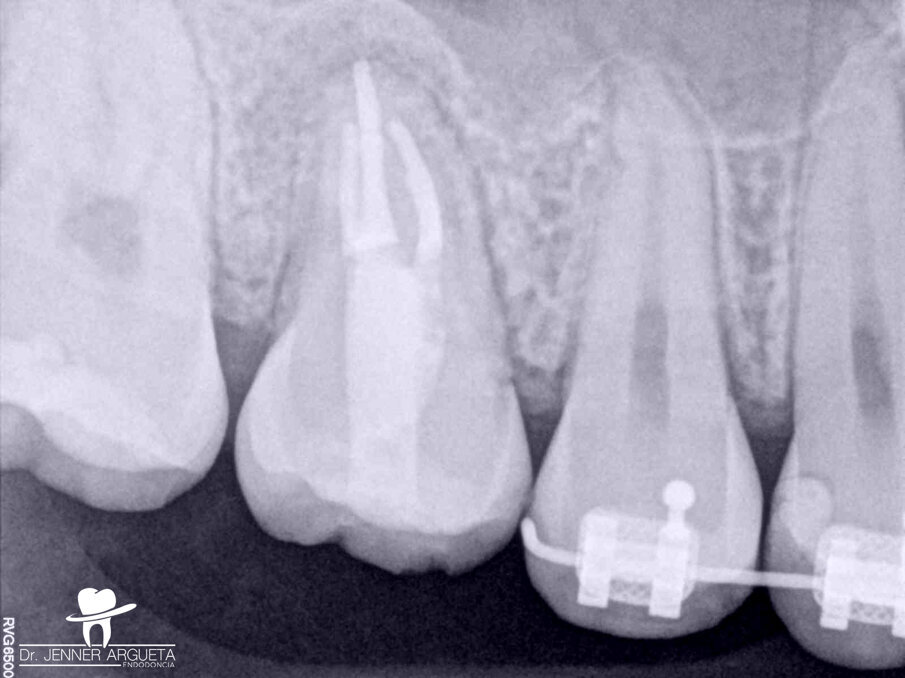

A 16-year-old female patient was referred to the office for evaluation of tooth #16 (Fig. 1). The referring dentist asked that we apply all the available resources to save the tooth. The diagnosis was previously treated and symptomatic periapical periodontitis. After detailed examination, it was concluded that the tooth was not restorable. With the parents’ and patient’s agreement, we decided on an autogenous transplantation of tooth #18 to the site of tooth #16 after its extraction (Fig. 2). The orthodontist had determined that tooth #18 was to be extracted, and it was intended that the patient’s occlusion should be balanced by the end of the orthodontic treatment. Teeth #16 and 18 were extracted in the least traumatic way possible. After minor bone remodelling of the socket using low-speed burs, the third molar was transplanted to the recipient site (Fig. 3). A nylon monofilament flexible splint was used to keep the tooth in place (Fig. 4). Fifteen days later, the splint was removed, healthy soft tissue was observed, the patient was asymptomatic, and the tooth was stable in the site (Figs. 5a & b).

Fig. 1: Severely destroyed maxillary first molar with an old amalgam restoration, previous root canal therapy and recurrent caries.

Fig. 2: Periapical radiograph of the maxillary right molar. Tooth #18 was to be transplanted to the site occupied by tooth #16.